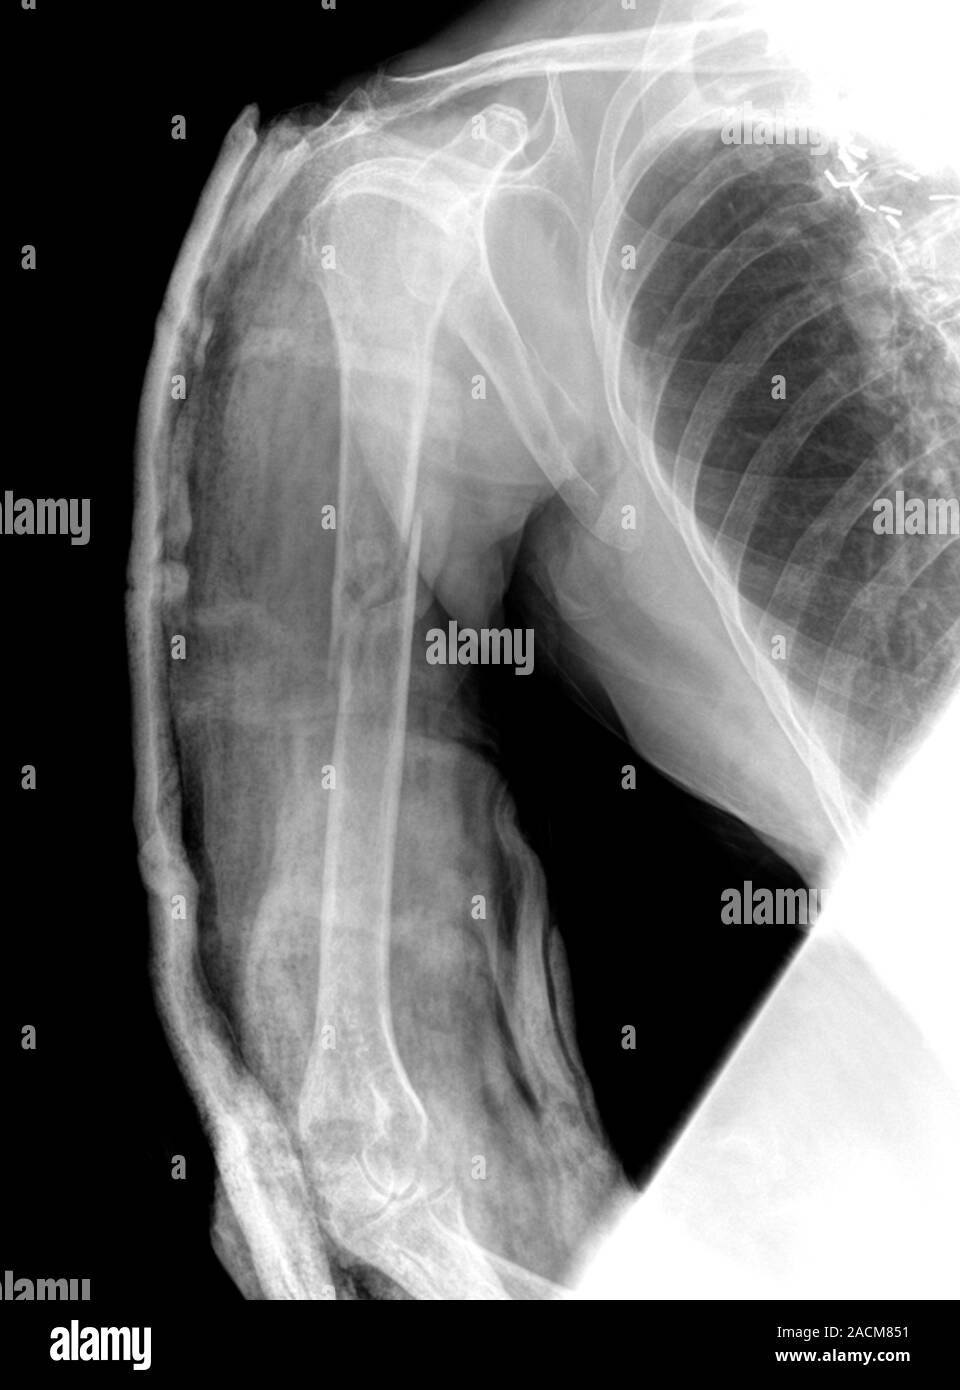

From www.alamy.com

Chest Xray (front view) showing a fracture to the arm bone (humerus Arm Bone Humerus Fracture There are several types of humerus fractures, depending on the location of the break. what is a broken arm? a humerus fracture is a break in the large bone of your upper arm. Symptoms may include pain, swelling, and bruising. a humerus fracture is the medical name for breaking the bone in your upper arm (your humerus).. Arm Bone Humerus Fracture.